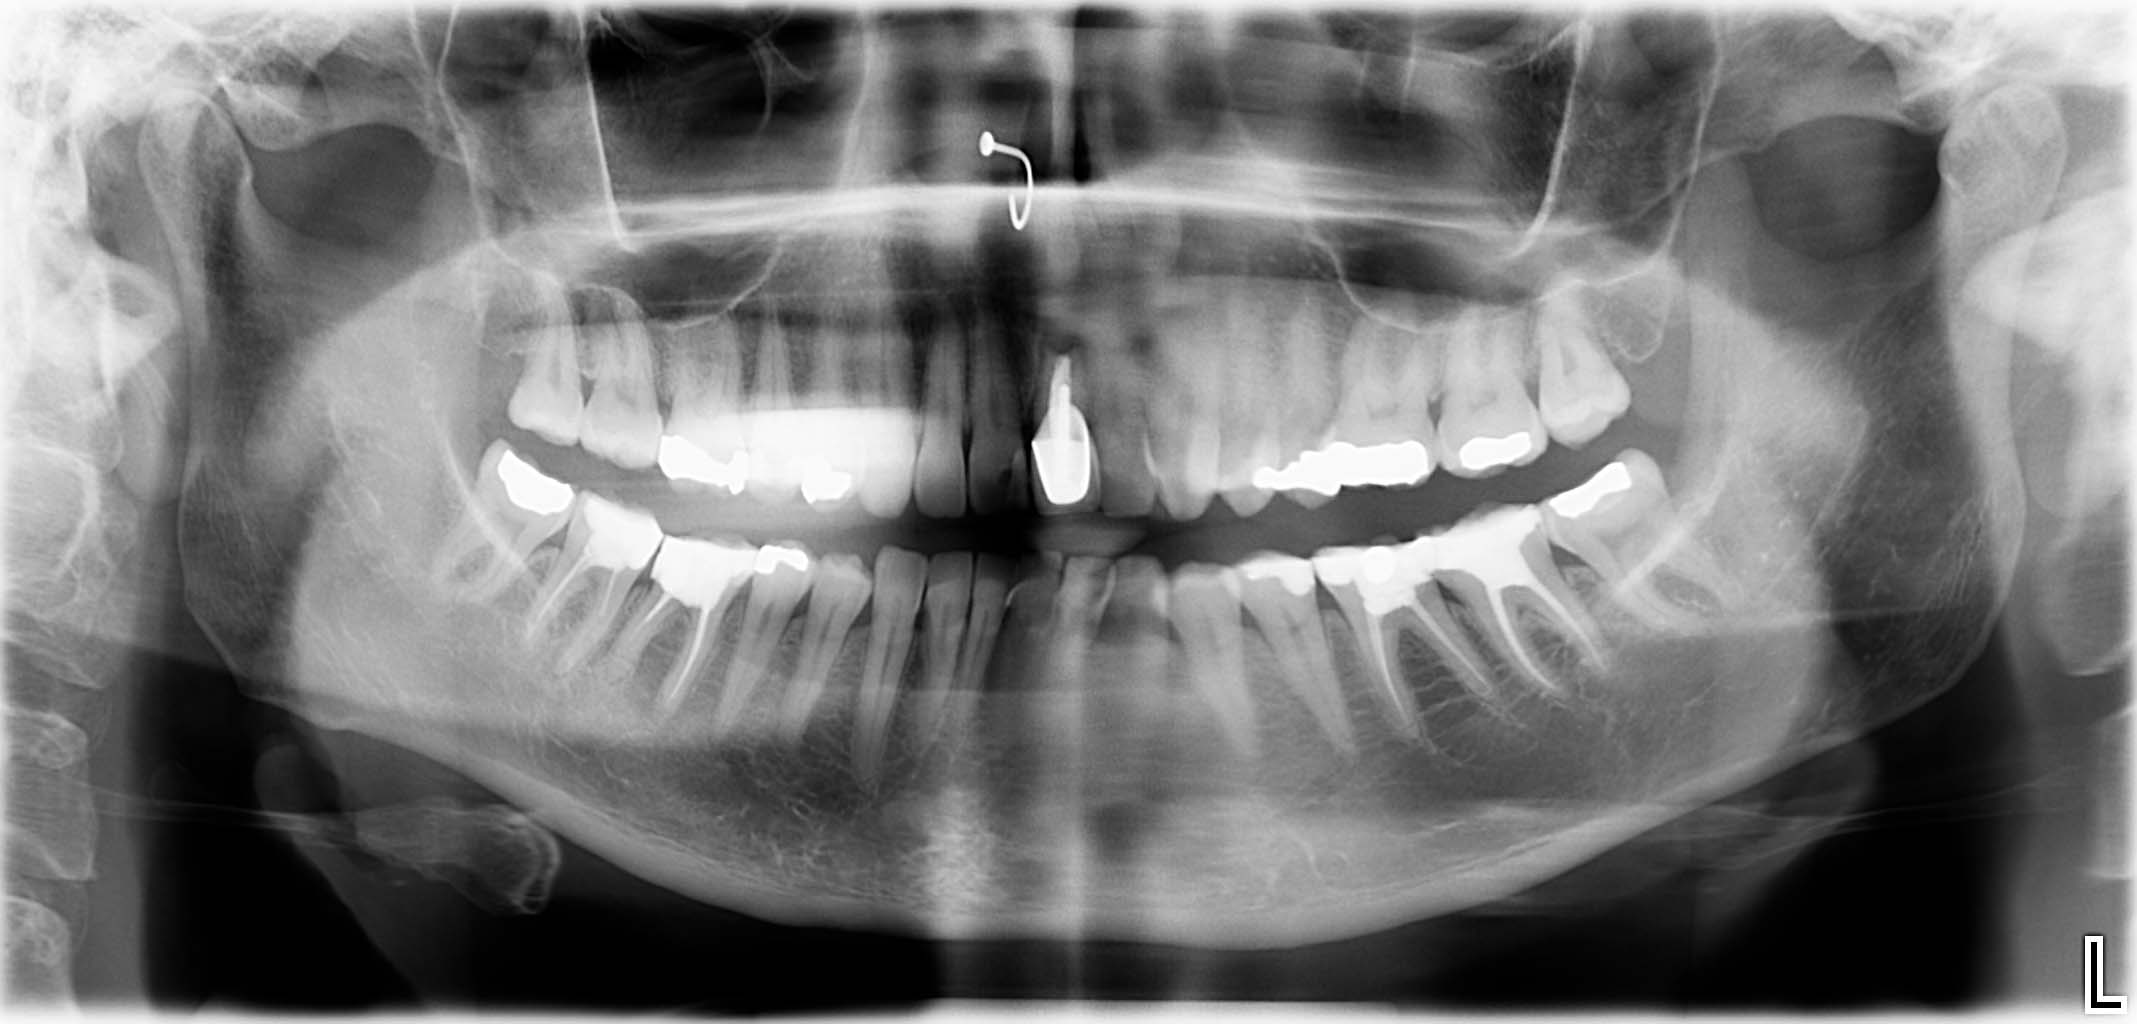

Ausgangssituation: Zahn 36 mit apikaler Beherdung, nicht erhaltungswürdig